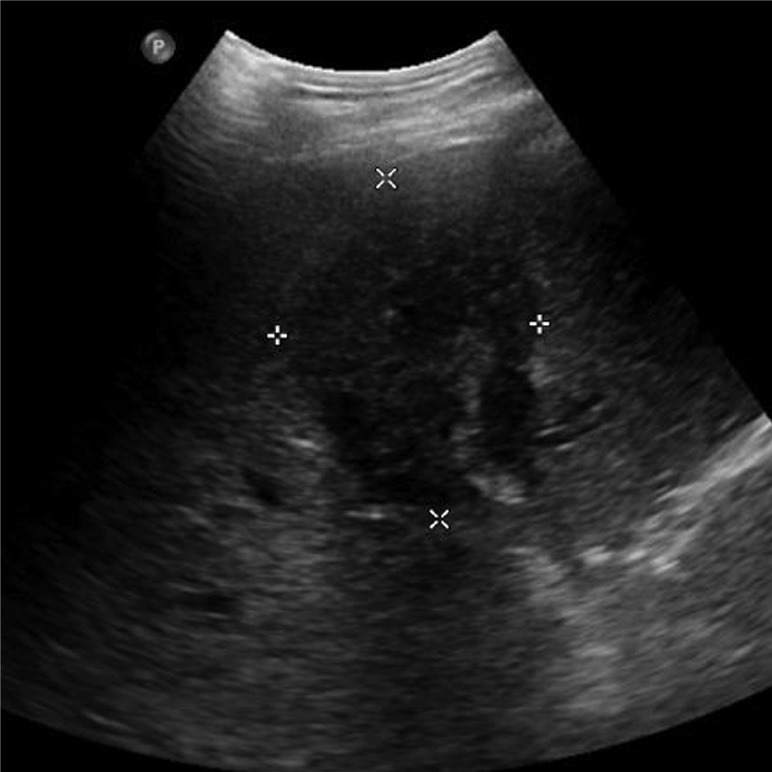

- Ecografia (US): rappresenta tipicamente la valutazione radiografica iniziale. È una tecnica non invasiva e a basso costo, molto efficace nel rilevare la dilatazione dei dotti biliari a monte dell’ostruzione. Tuttavia, la sua sensibilità nel localizzare con precisione il sito dell’ostruzione e nel definire l’estensione del tumore, in particolare l’invasione vascolare e linfonodale, è limitata.